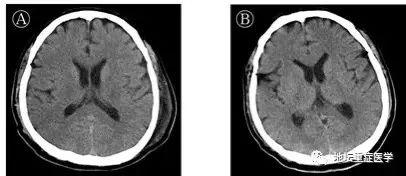

许先生1月24日以新冠肺炎、危重型、呼吸衰竭收入院。入院后给予联合干扰素雾化、抗病毒治疗,预防细菌感染,并给予中医辨证用药。未见好转,高热,乏力,呼吸困难逐渐加重。1月27日(起病第10天)胸部CT显示双肺磨玻璃密度影范围扩大,部分实变影。短暂予经鼻高流量吸氧,其呼吸窘迫无缓解,烦躁不安,呼吸50次/分,氧分压85%,在ICU进行气管插管,按照重度呼吸窘迫综合征(ARDS)的呼吸通气原则进行机械通气。治疗96小时后(起病第14天),患者出现颌面及口角频繁抽搐,伴持续呃逆,医生查体发现颈抵抗阳性,双侧瞳孔等大等圆,对光反射迟钝,四肢肌张力升高,双侧膝反射亢进,双侧巴氏征及踝阵挛阳性,头颅CT颅内未见异常,测脑脊液压力大于330mmH2O,脑脊液外观无色清亮,生化检测无异常。北京地坛医院重症医学科、检验科及中国疾控中心传染病所联合工作组对采集的脑脊液标本进行宏基因组二代测序、鉴定可能的感染病原体过程中,排除了其他病原体,获得了SARS-CoV-2病毒基因组序列。通过基因测序证实脑脊液中存在SARS-CoV-2,临床诊断病毒性脑炎。